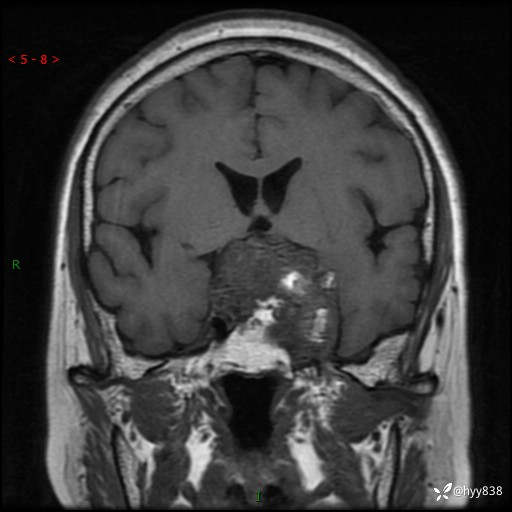

T1WI cor

鞍区MRI平扫

临床诊断:鞍区肿物